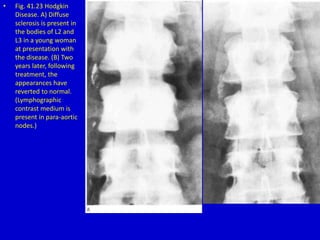

• Fig. 41.23 Hodgkin

Disease. A) Diffuse

sclerosis is present in

the bodies of L2 and

L3 in a young woman

at presentation with

the disease. (B) Two

years later, following

treatment, the

appearances have

reverted to normal.

(Lymphographic

contrast medium is

present in para-aortic

nodes.)

• Fig. 41.23Hodgkin Disease. A) Diffuse sclerosis is present in the bodies of L2 and L3 in a young woman at presentation with the disease. (B) Two years later, following treatment, the appearances have reverted to normal. (Lymphographic contrast medium is present in para-aortic nodes.)